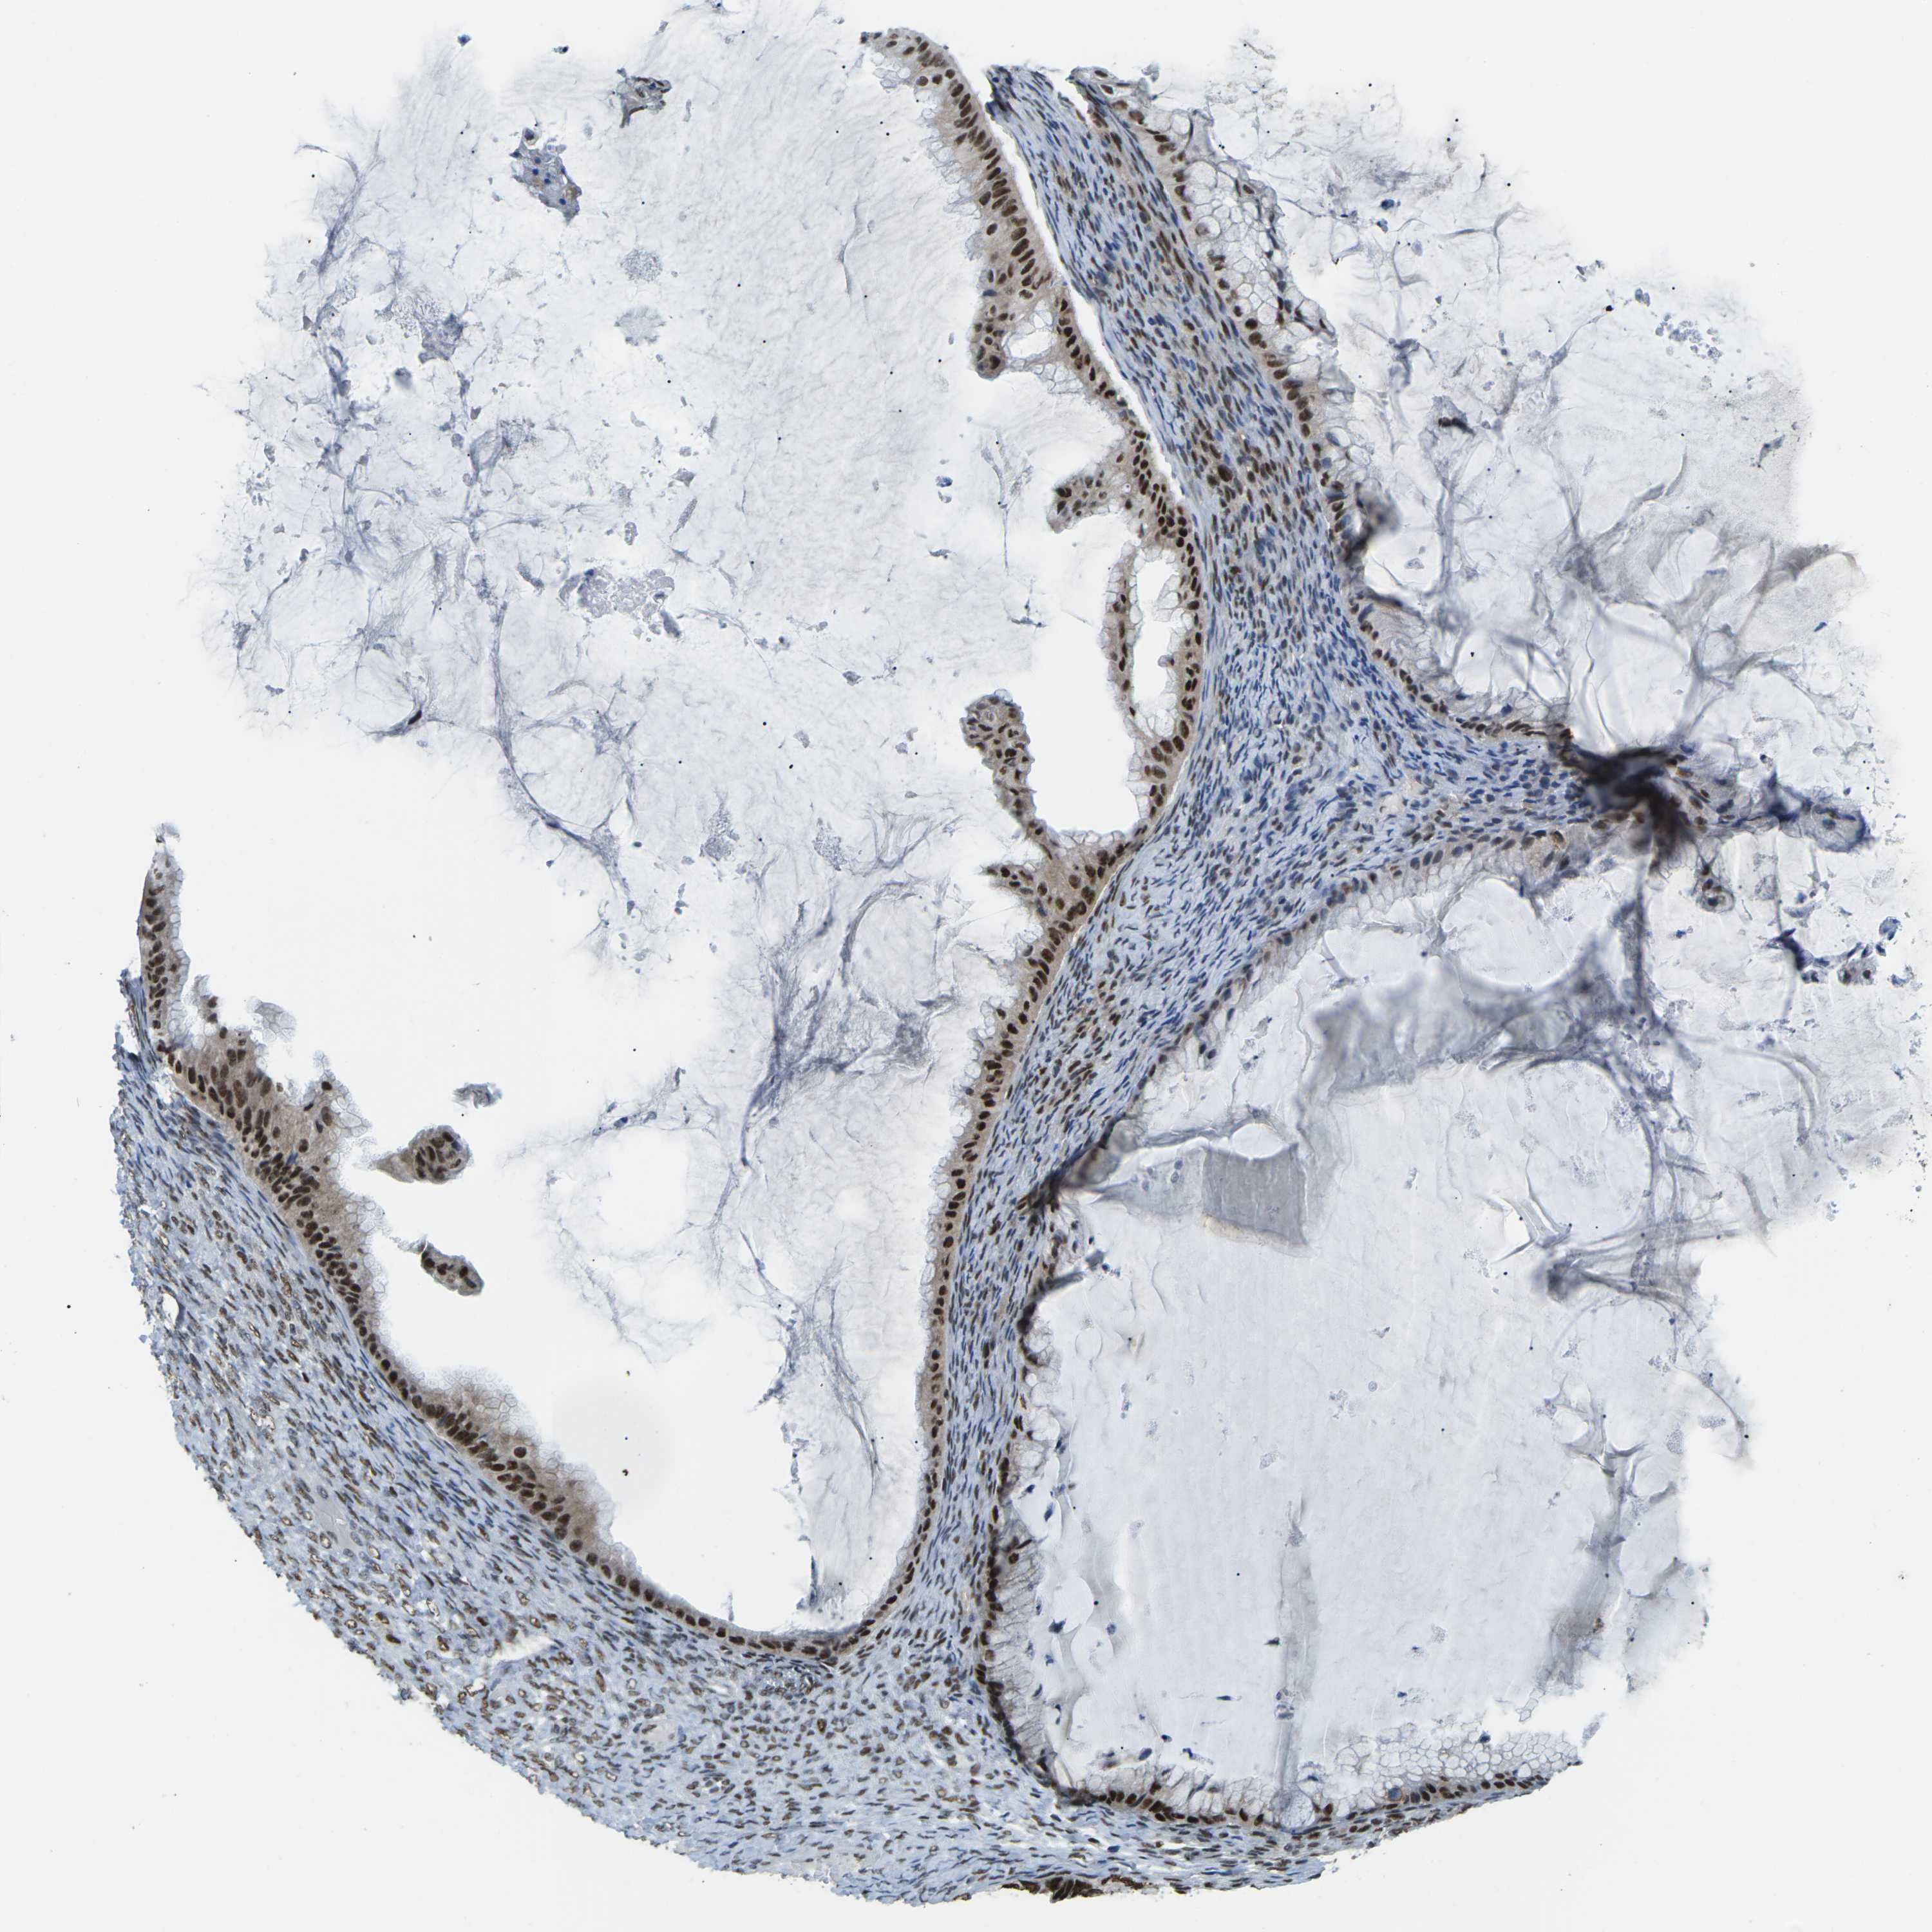

OVARIAN CANCER - Protein expressioni

A mouse-over function shows sample information and annotation data. Click on an image to view it in a full screen mode. Samples can be filtered based on level of antibody staining by selecting one or several of the following categories: high, medium, low and not detected. The assay and annotation is described here.

Note that samples used for immunohistochemistry by the Human Protein Atlas do not correspond to samples in the TCGA dataset.

Antibody stainingi

Antibody staining in the annotated cell types in the current human tissue is reported as not detected, low, medium, or high, based on conventional immunohistochemistry profiling in selected tissues. This score is based on the combination of the staining intensity and fraction of stained cells.

Each image is clickable and will lead to virtual microscopy that enables deeper exploration of all samples and also displays staining intensity scores, fraction scores and subcellular localization as well as patient and tissue information for each sample.

Antibody HPA012510

Antibody CAB008388

Cystadenocarcinoma, serous, NOS

Carcinoma, endometroid

Cystadenocarcinoma, mucinous, NOS

Carcinoma, NOS